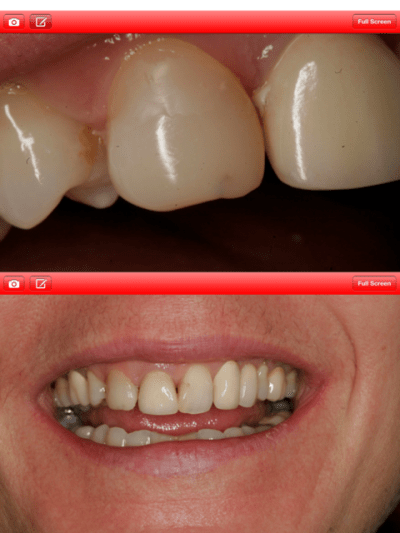

Oui bord cervical de la 21 trop coronaire et bord cervical de la 22 trop apical.

Cela ne gene pas la patiente qui n'a pas envie que je ré-intervienne.

Le cas est fini, mais je trouve le travail du labo bof. acceptable est accepté par la patiente mais bof!

Je ferai les photos finales lors du contrôle.

Voila c'est fini, mais je suis critique sur plusieurs points:

- La qualité des CCM qui est pas super mais faite par le labo qui ma référé la patiente.

- La 11 dont le collet s'est un petit peu rétracté et laisse apparaître la racine par transparence. J'aurais souhaité faire un lambeau tracté coronairement , mais pas la patiente qui est très satisfaite.

- Le collet de la 22 trop apical, à cause de l'élongation coronaire trop apicale.